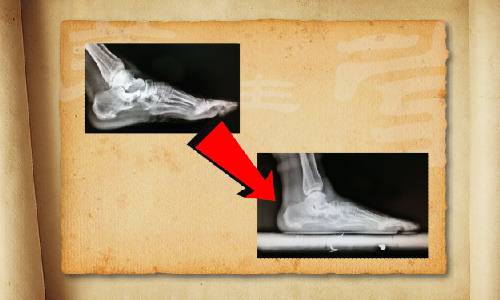

很多足部的疾病,都是因?yàn)檫x鞋不當(dāng)而導(dǎo)致的。有人做過(guò)統(tǒng)計(jì):70%的人一生中有過(guò)腳病。比如腳部皮膚病變,真菌感染引起"腳氣";還可能受到各種損傷,引起骨折和肌腱的斷裂,或者出現(xiàn)后天性畸形;更為嚴(yán)重的是,腳部疾病還會(huì)導(dǎo)致腰、背等全身骨骼肌肉的問(wèn)題。更多精彩內(nèi)容敬請(qǐng)收看北京衛(wèi)視《養(yǎng)生堂》—《選鞋選健康》。

很多老年人覺(jué)得穿布鞋是最舒服的,其實(shí)布鞋以及一些沒(méi)有足弓支撐的拖鞋、涼鞋,都會(huì)導(dǎo)致足部的內(nèi)側(cè)疼痛,進(jìn)而造成足弓的損傷,最常見(jiàn)的是走路時(shí)間長(zhǎng)了開(kāi)始腳疼。如果您疼痛的部位,出現(xiàn)在腳掌中指下部、拇指跟部、小指跟部、中指關(guān)節(jié)處這些地方,您要千萬(wàn)注意了。更多精彩內(nèi)容敬請(qǐng)收看本期節(jié)目。

我們都知道買(mǎi)鞋得看號(hào)碼,有經(jīng)驗(yàn)的人買(mǎi)鞋會(huì)更有經(jīng)驗(yàn),比如皮鞋會(huì)買(mǎi)大一號(hào),穿起來(lái)寬松;運(yùn)動(dòng)鞋呢就盡量合腳一些。但是大多數(shù)人不知道的是,買(mǎi)鞋不光要看鞋號(hào),還要看鞋型。要依據(jù)自己的腳型來(lái)匹配買(mǎi)鞋。